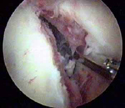

Βλάβη Bankart πριν και μετά απο την αποκατάσταση

κινητοποίηση της βλάβης (αποκόλληση του επιχειλίου χόνδρου) (0.66MB)